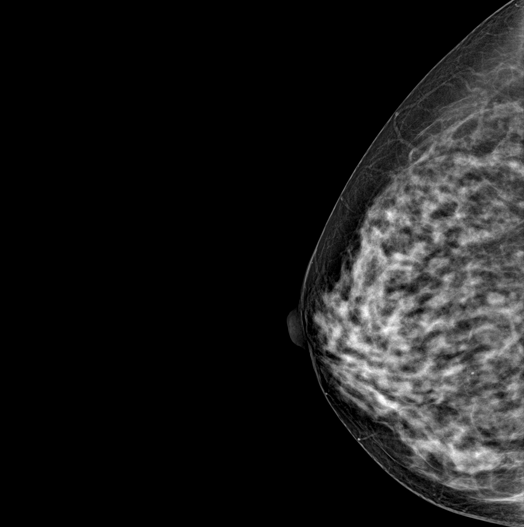

SYNTHESIZED 2D

HESTIA supports "Synthetic 2D" that generates 2D images only by tomography shooting without additional 2D shooting.